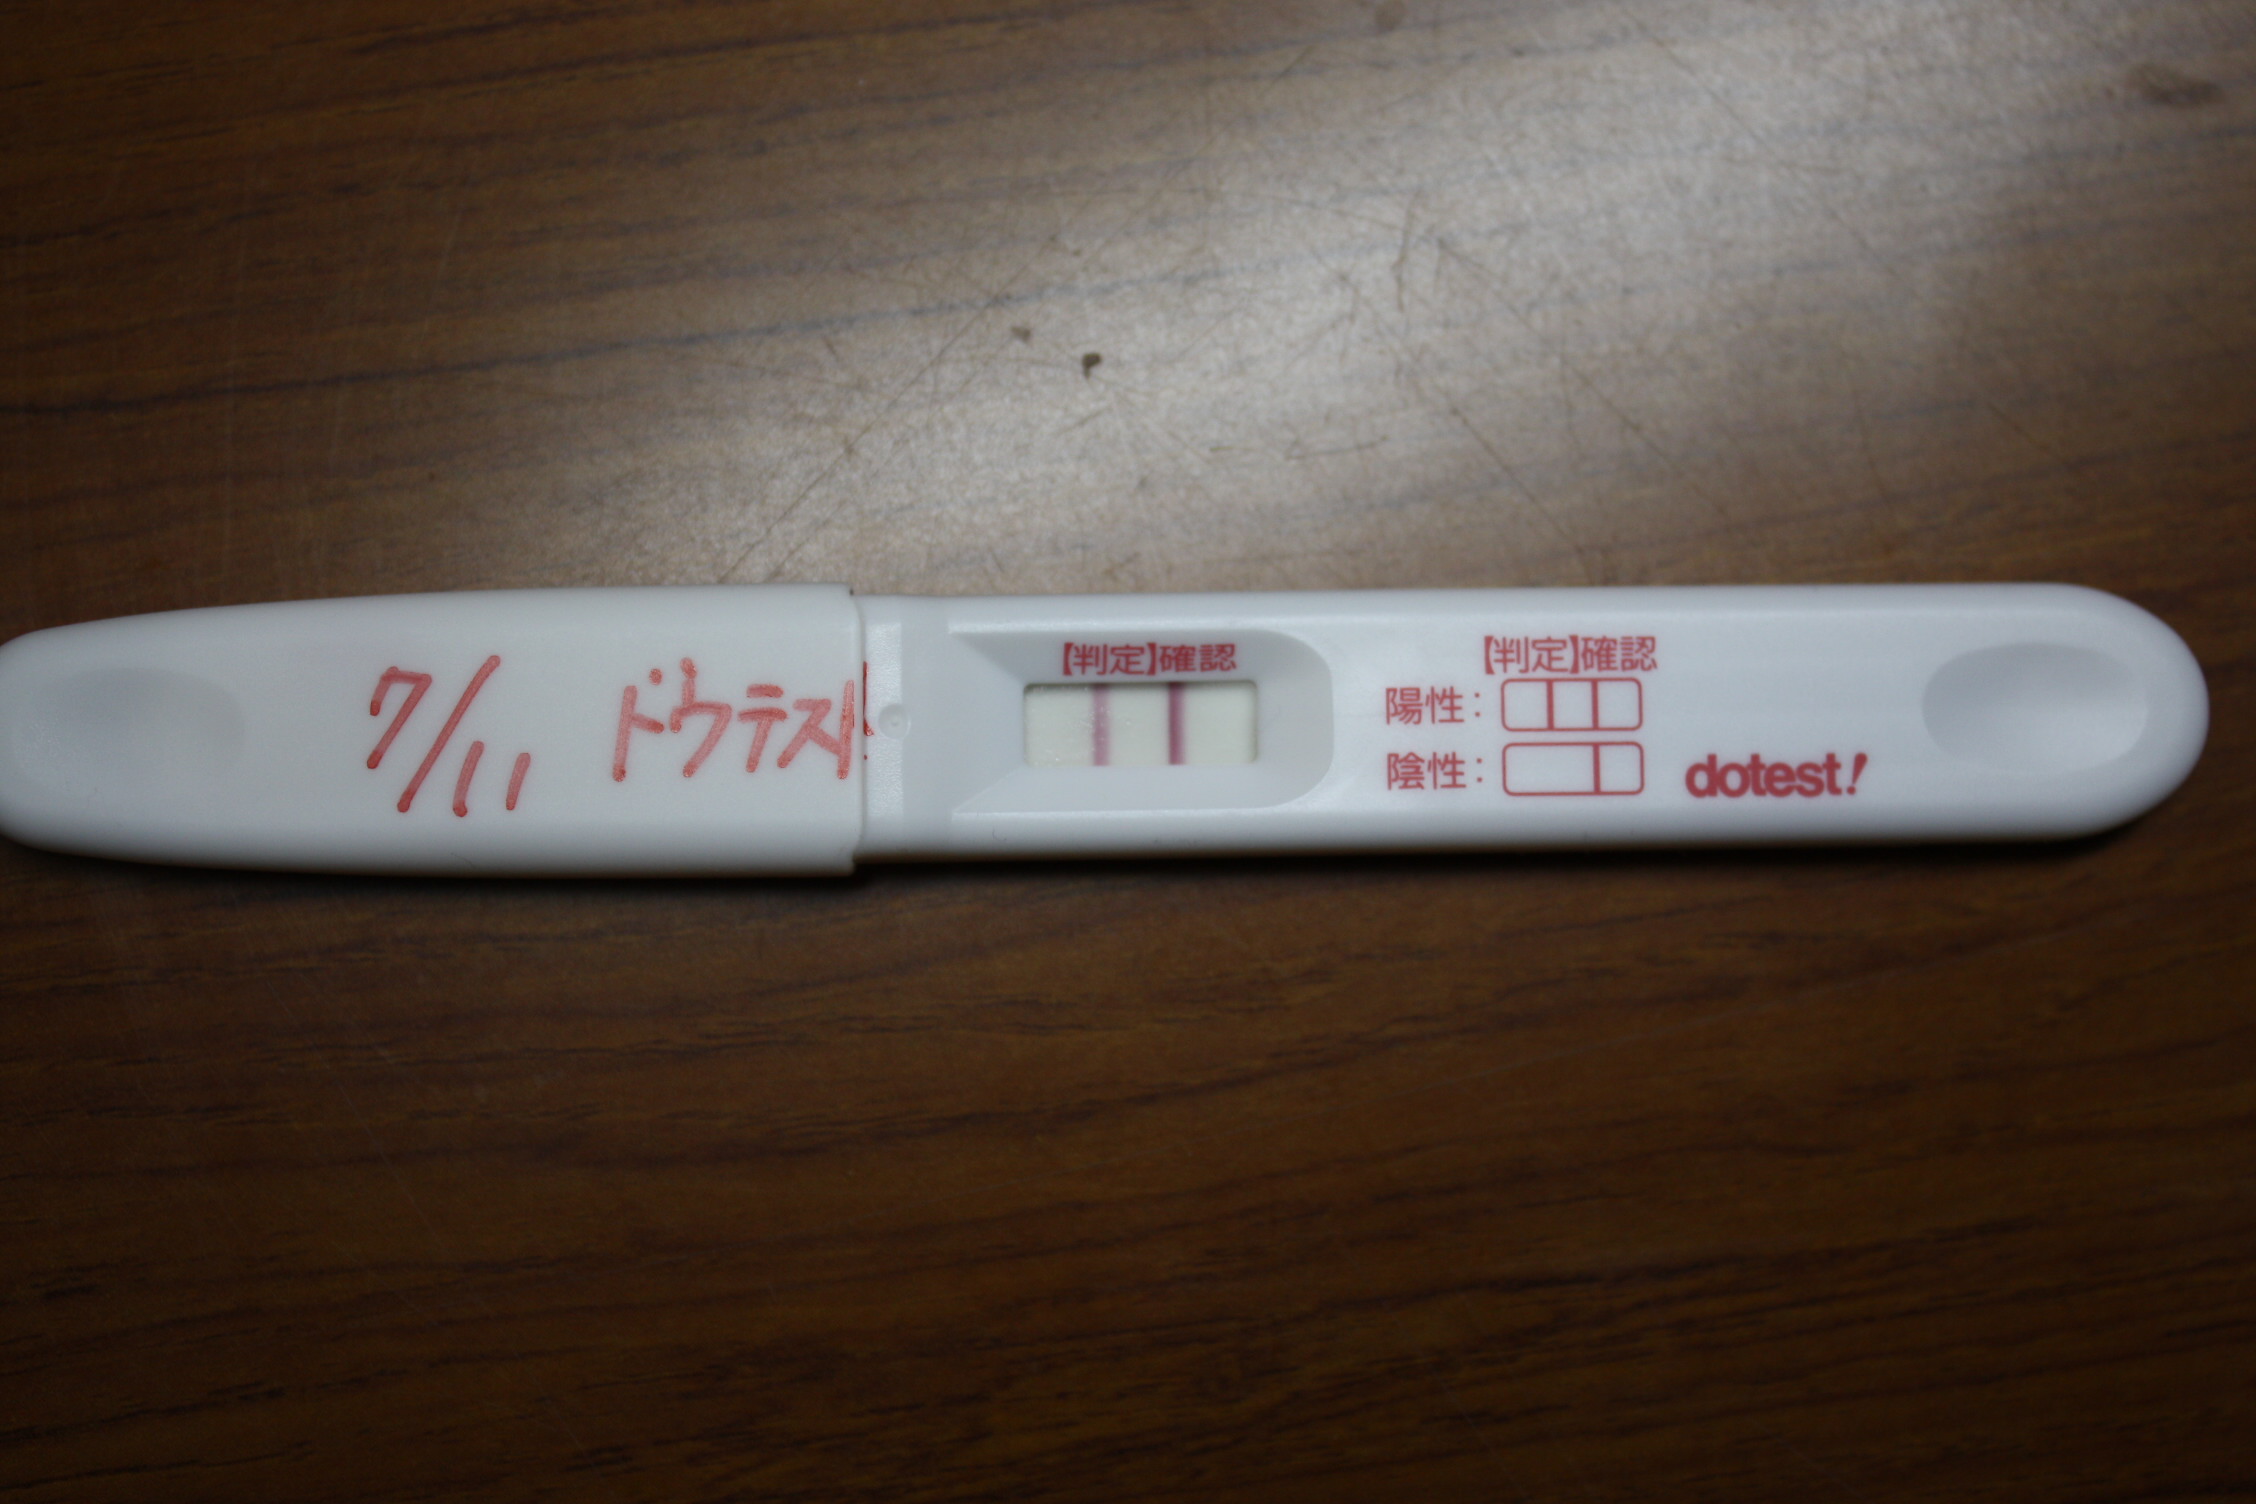

妊娠4週 妊娠検査薬陽性と初めての受診 2人姉妹をもつ多趣味主婦とみのblog

初診 ドゥテスト 16日目 4週0日 2人目妊娠日記

妊娠検査薬の反応について 妊娠4週あたりだと思いますが エンジ Yahoo 知恵袋

妊娠しました 最終月経から陽性 初診までまとめました 妊娠4週目 ポチレビュー

妊娠4週目 フライング検査薬 特定不能の広汎性発達障害 ハルの療育記録

妊娠4週目 最後の妊娠検査薬 娘とあたしの生活 妊娠 出産 バタバタ子育て始まり おたまママのブログ

妊娠4週の口コミ 初期症状とフライング検査 産婦人科の選び方 たまひよ

検査薬で妊娠がわかった5週目 頭痛につわり肌荒れ対策のポイントも ちびもんひみつきち 未婚シンママ妊婦生活